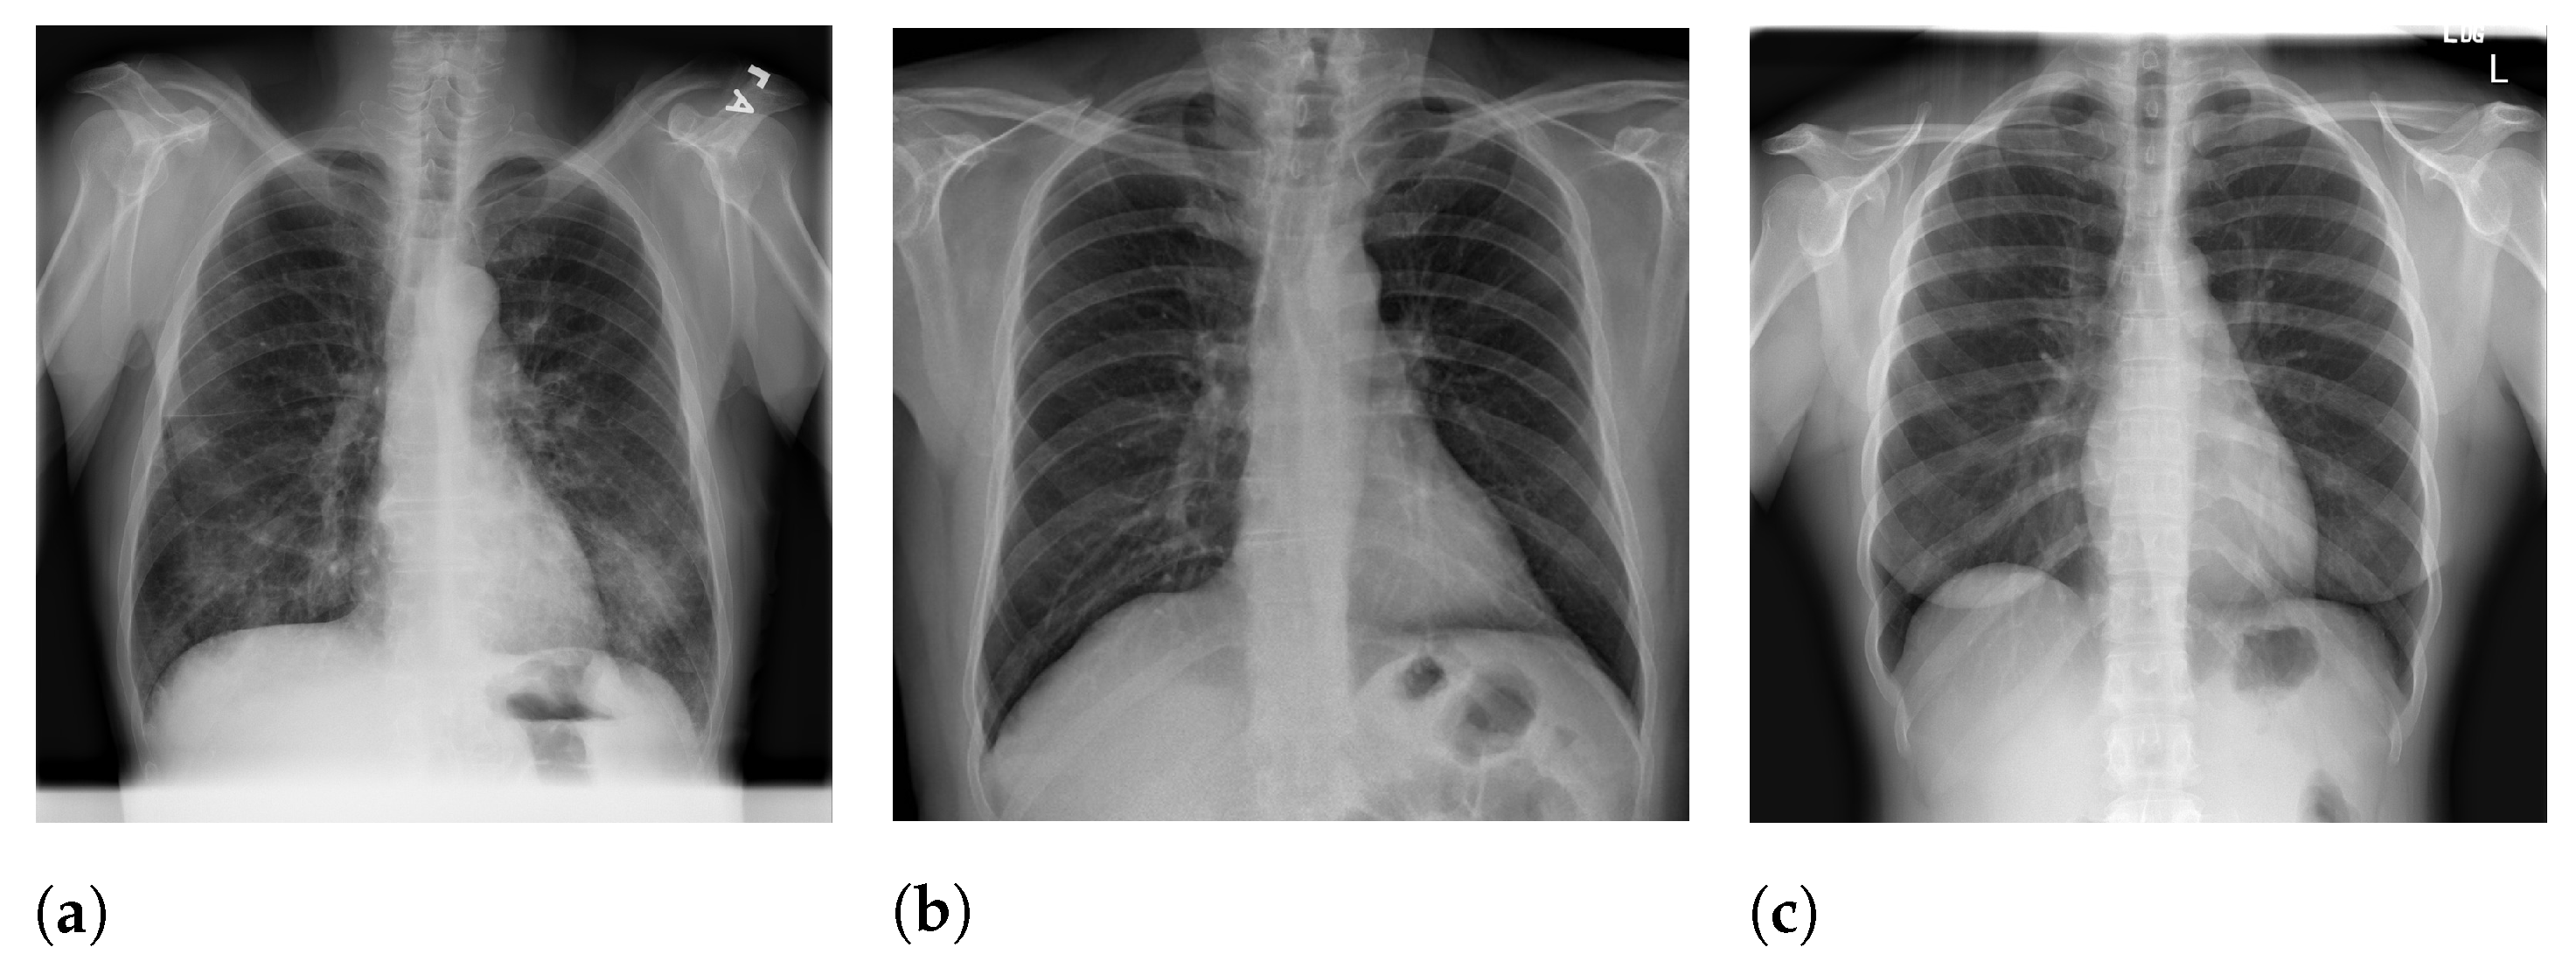

Figure 3 presents an example of CXR images with burned-in information.

Figure 5 presents image examples for each class retrieved from the RYDLS-20-v2 database.